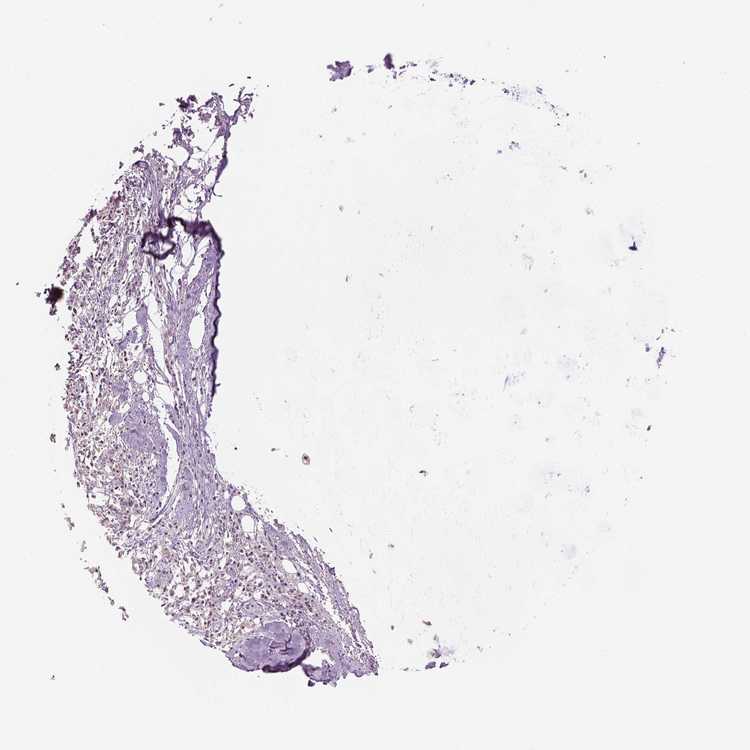

SOFT TISSUE 1 - Antibody stainingi

Antibody staining in the annotated cell types in the current human tissue is reported as not detected, low, medium, or high, based on conventional immunohistochemistry profiling in selected tissues. This score is based on the combination of the staining intensity and fraction of stained cells.

Each image is clickable and will lead to virtual microscopy that enables deeper exploration of all samples and also displays staining intensity scores, fraction scores and subcellular localization as well as patient and tissue information for each sample.

Antibody HPA067740

Chondrocytes Low

Fibroblasts Not detected

Peripheral nerve Not detected